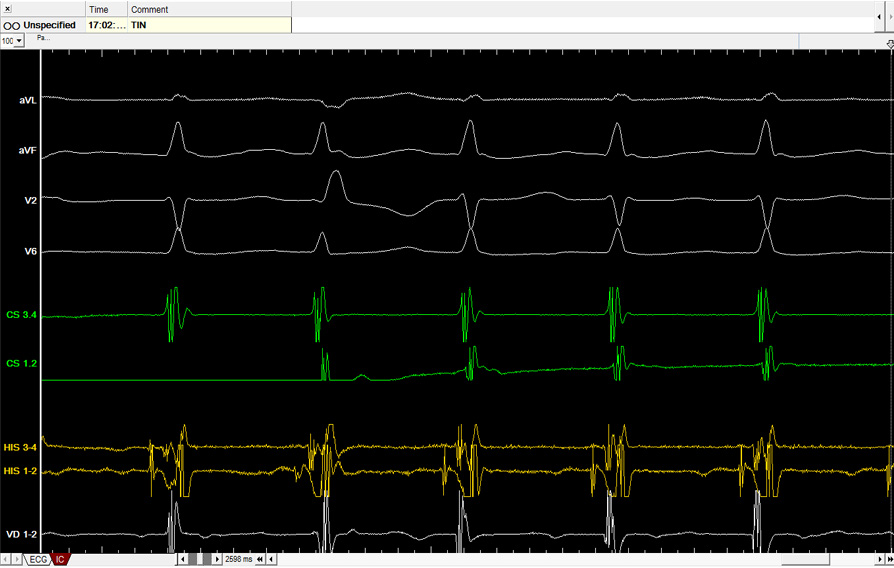

Entre ellas se encuentran la taquicardia intranodal y la taquicardia mediada por vías accesorias (Wolff-Parkinson-White), que se caracterizan por episodios repetidos y bruscos de palpitaciones, habitualmente en pacientes jóvenes o de edad media. También se agrupan con este nombre la taquicardia auricular y el flutter auricular.